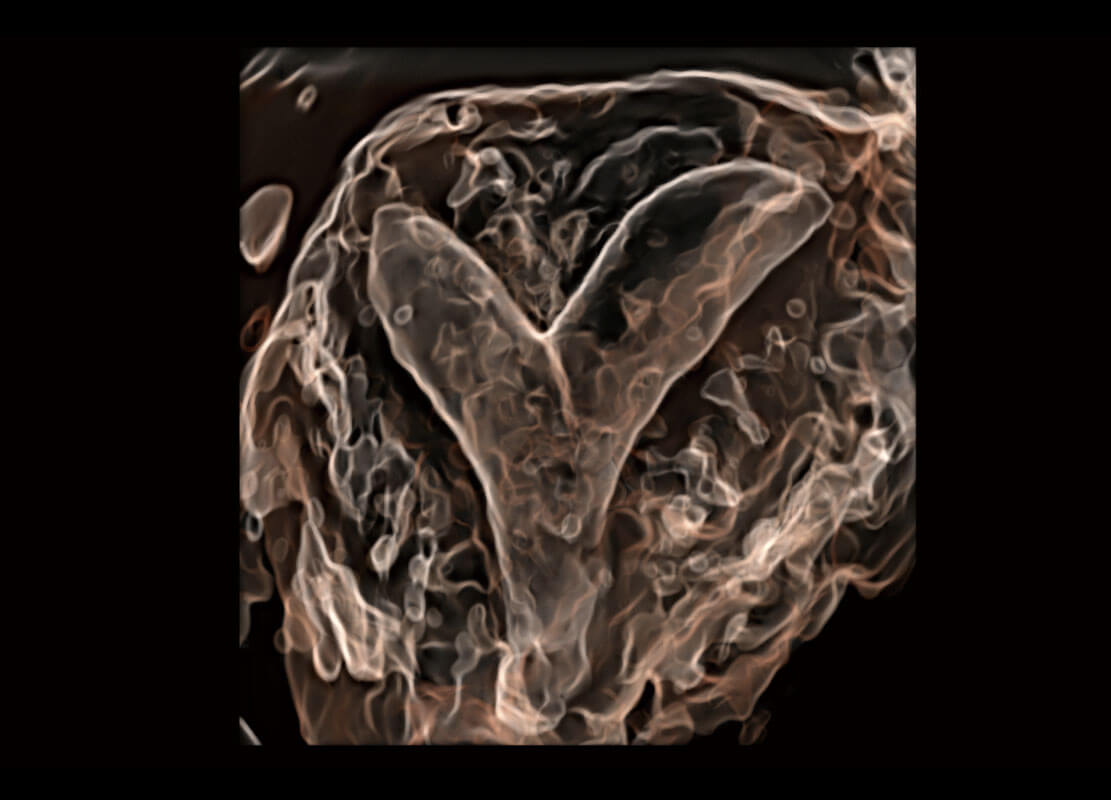

生殖健康

P60优异的图像质量搭载专科探头,在妇科基础疾病的诊断、卵泡生长的监测、输卵管通畅情况的判别等方面为您提供生殖应用方案。

• 腔内三维-宫内节育器

• 腔内三维-光影成像